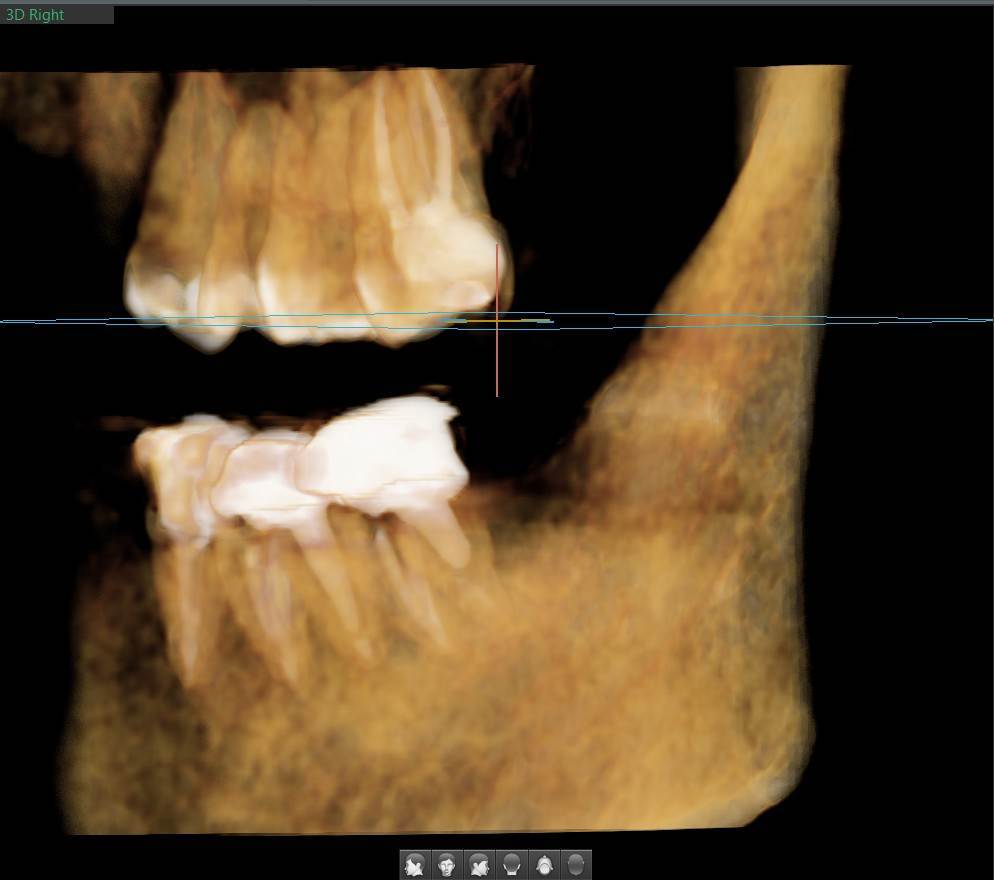

A-V-S Опубликовано 3 марта Поделиться Опубликовано 3 марта Здравствуйте. У меня такая ситуация: В начале января 2026 начал болеть зуб 7ка снизу слева - боль развивалась постепенно - в итоге стало больно жевать. Сделал КТ. Лечащий стоматолог сказал, что это проснулось спящее воспаление, перелечивать каналы зуба сложно - надо сверлить буром и доставать стекловолоконный штифт - надо удалять. В следующие дни открылся свищ и боль ушла. Свищ продолжает быть с периодическим набуханием и сдуванием после выброса гноя белого цвета. Этот зуб лечили с установкой стекловолоконного штифта чуть больше 5 лет назад. Посмотрите, пожалуйста, приложенные снимки и посоветуйте как быть - можно ли перелечить и сохранить зуб ? Ссылка на комментарий

АнтонТЛТ Опубликовано 3 марта Поделиться Опубликовано 3 марта Добрый вечер, лучше выложить несколько срезов этого зуба, либо архив с кт. По представленным снимкам, есть подозрение о наличии трещины между корнями зуба. 1 1 Ссылка на комментарий

A-V-S Опубликовано 4 марта Автор Поделиться Опубликовано 4 марта Здравствуйте. @АнтонТЛТ , добавил. Ссылка на комментарий

red_butler Опубликовано 4 марта Поделиться Опубликовано 4 марта Здравствуйте, Вы выложили не срезы. а реконструкцию. Залейте кт в облако и скиньте сюда ссылка на скачивание Ссылка на комментарий